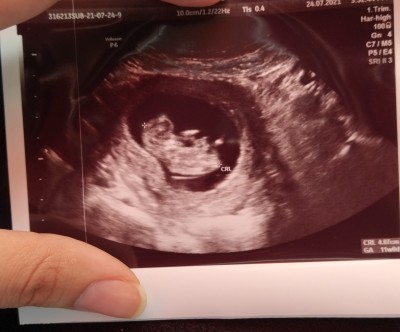

image

kizlar okudum ama nub teorisini pek anlamadım anlayan yazabilir mi lütfen :)

Nub teorisi bilmem ama bu kız canım insallah:))

Bebeğin kız canım. Nuba göre de kız.

Kizlar resim o anki ultrason ne yöne baktigi ile alakalı resim atabilirim aynı gün almıştım 2 tane resim birinde Yuvarlar diğeri sivri

Bebeğin bası sol da kız gibi ama kesen erkek diye bağırıyor.

bunlar ilk hamileligimden ki resimler sağ üstte aynı tarihten olduğunu görebilirsiniz yani alakası yok kese sekli vs şimdi siz bu bebeğe ne derdiniz kız mı erkek mi